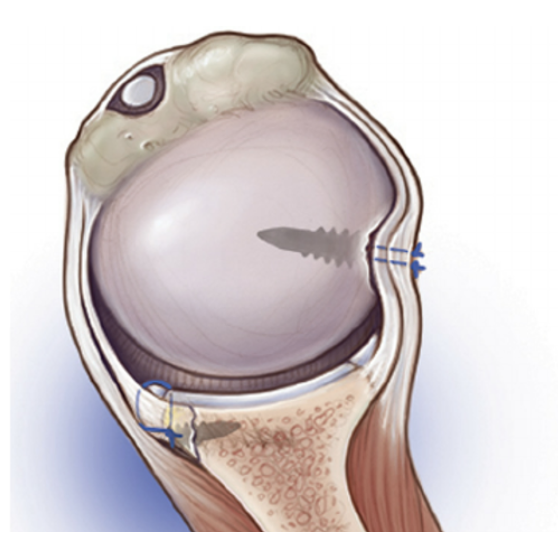

By November, Ms C was prepared and ready. The surgery involved a Right Bankart repair with “knotless” Remplissage. The image below is provided by Mr Wang in the patient-information with the following explanation of the procedure.

(https://www.kemblewang.com/bankart-remplissage)

“The Bankart repair refers to repair of the labral tear, and the Remplissage procedure refers to filling up of the divot with soft tissue (like filling in a pothole on the road). Whilst the Bankart repair is the mainstay of the procedure, Kemble sometimes adds a remplissage to improve stability, especially in young/adolescent patients. The following is a schematic diagram of such a procedure.”

Here is an additiona link to a video of the surgical techniques used.